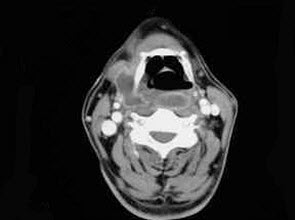

10、单项选择题

如图,出现咽旁脓肿侵蚀颈动脉可引起()。